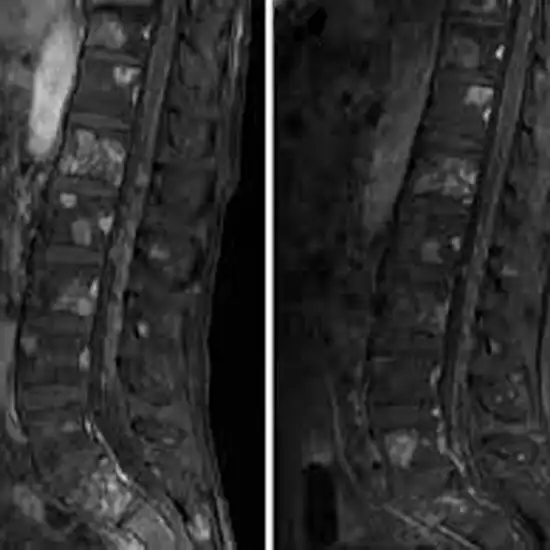

MRI of the Sacral Spine is used to see the sacrum, a triangular bone at the end of the spine, and the soft tissues, such as muscles, surrounding it.

The doctor orders this test to find out what is causing lower back pain (lumbago), sciatic pain, or inflammation of the lumbosacral joints, as well as to see if there is a tumour or other abnormal growth in the lumbosacral vertebrae or the soft tissues around them.